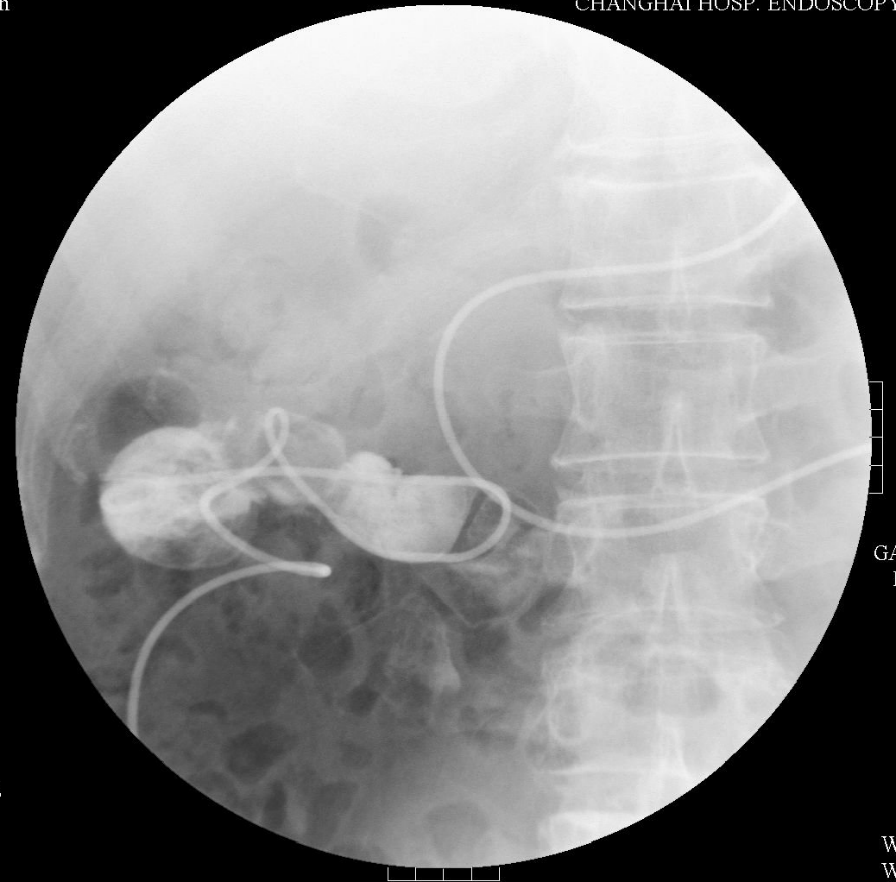

X线透视下亦可见鼻胆管迅速往肛侧滑动。(图5)

图5